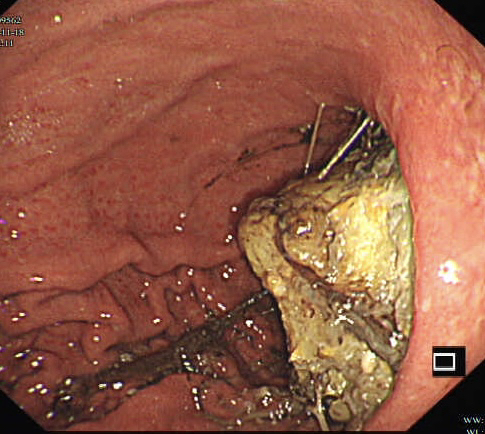

第二个病例,青年男性,也是突然腹痛,症状和第一个类似,首选腹部CT。

胃镜证实